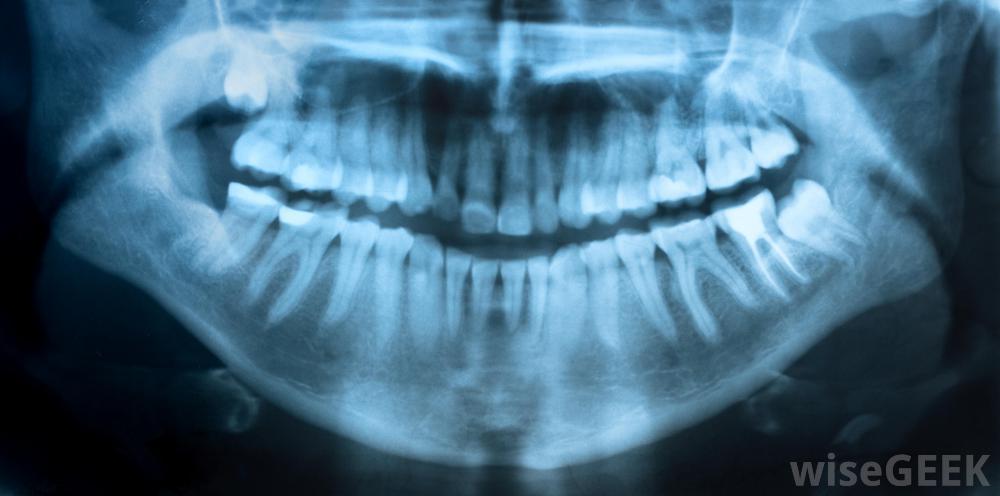

一般來說,懷孕期間做根管是安全的。根管是指從病人牙齒上切除受損的神經和牙髓。通常情況下,在懷孕期間,婦女在根管治療之前、期間或之后需要進行的x光檢查是一個令人擔憂的問題,但通常并不代表有顯著的風險。婦女通常擔心用于麻醉口腔做根管的藥物,但它們通常也是安全的。此外,婦女不必擔心用于沖洗的化學物質或根管期間使用的樹脂,因為它們通常不會傷害發育中的胎兒X光檢查是根管治療的一部分,很多人認為懷孕期間做根管治療是危險的,應該盡量避免,在懷孕期間做根管通常是安全的。事實上,有根管有助于保護發育中嬰兒的健康。這是因為一顆不健康的牙齒如果不治療,可能會嚴重感染。這種類型的感染有可能變得非常嚴重,影響到身體的其他部分,但是治療牙齒有助于消除這種風險。懷孕期間做根管通常是安全的婦女在懷孕期間患根管的主要問題可能是需要進行x光檢查然而,在大多數情況下,對發育中的孩子的風險是最小的。根管治療所需的x光片是針對婦女的口腔而不是腹部,因為這可能會影響到她的孩子。此外,如果婦女懷孕期間需要x光檢查,牙醫可能會提供一件鉛背心來保護腹部,不過,牙醫通常建議婦女等到分娩后才進行常規x光檢查;只有那些絕對必要的根管手術或其他牙科手術通常是在懷孕期間進行的。如果需要根管治療,母親和嬰兒都會更健康就根管治療中使用的藥物和化學物質而言,大多數被認為是安全的。懷孕期間用于根管麻醉的藥物通常不會穿過胎盤或傷害發育中的胎兒。用于沖洗患者口腔的液體可能含有鹽酸鈉或類似的化學物質,同樣的,在根管發育過程中使用少量的樹脂也不會對胎兒的健康造成威脅引起極度痛苦的名聲女性懷孕期間患根管的主要問題可能是需要x光片;牙齒不會暴露在危險的輻射水平下。牙科醫生使用根管切除患病或感染的牙齒的神經和牙髓;通常對孕婦是安全的。根管治療期間使用的藥物不知道會穿過胎盤影響嬰兒。